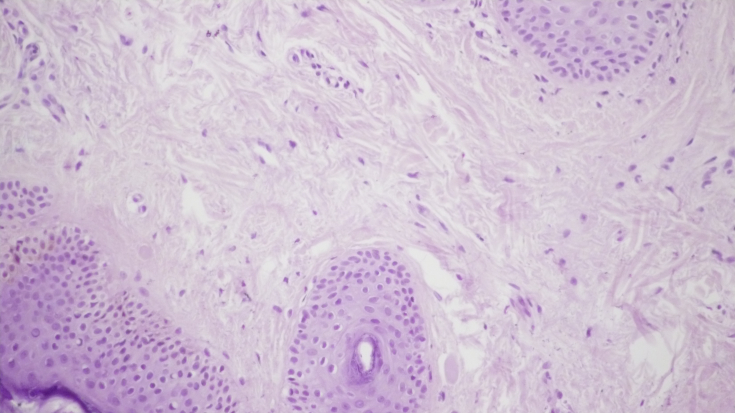

У шкірі пацієнта після монотерапії пептидним препаратом спостерігалося значне зниження запальної інфільтрації (мал. 2а, b). Спостерігалася незначна, переважно периваскулярна лімфоїдна інфільтрація клітин, рідше з'являлися окремі комплекси запальних елементів, розташовані біля придатків шкіри.

Малий. 2. Морфологічна картина шкіри після введення пептидного препарату: запальна інфільтрація дермі виражена набагато менше, х200; у дермі дрібні капіляри зі слабкою периваскулярною лімфоїдно-клітинною інфільтрацією, х200.